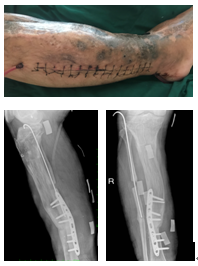

李斌主任及管床医生对其进行了详细的询问病史、查体、阅片后,制定了手术方案。2019年04月04日2小时45分钟的右胫骨后路清创钢板内固定+胫腓骨桥接植骨+腓骨植骨克氏针内固定手术顺利完成,术后予以抗感染对症治疗,患者切口愈合好,干燥无渗出,予以出院,定期复查。

术前:

术后: